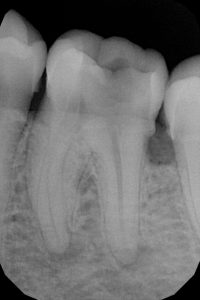

TREATMENTS

SERVICES

| 19 | Root Canal Treatment Conventional |

| 20 | Rotary RCT |

| 21 | Root Canal Treatment With Thermafil |

| 22 | Root Canal Treatment With Obtura (II) |

| 23 | Root Canal Treatment With Calamus |

| 24 | Regenerative Endodontics |

| 25 | Surgical Endodontics (Microscope) |